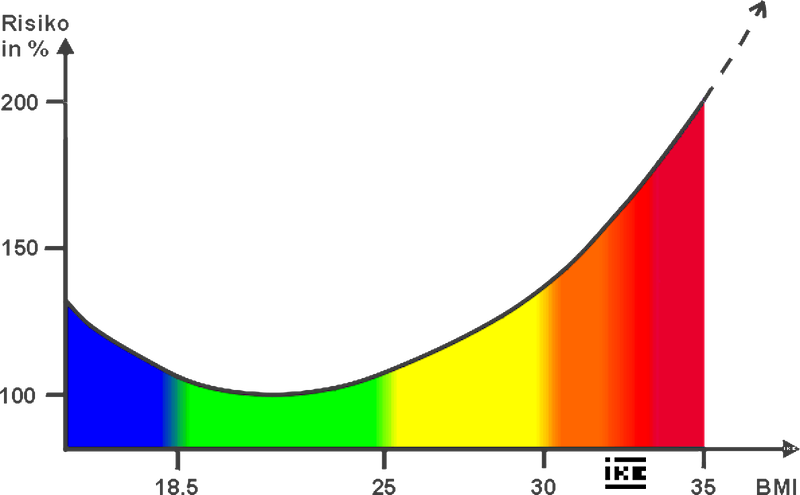

BMI

BMI bedeutet Body-Mass-Index und soll das Gewicht in Verhältnis zur Körperlänge bewerten. Ich habe das programmiert, um mich in Cookies einzuarbeiten.

Herausgekommen sind Lob oder Beschimpfung des Besuchers und eine Plausibilitätsprüfung. Das allerdings funktioniert erst beim wiederholten Besuch der Seite.